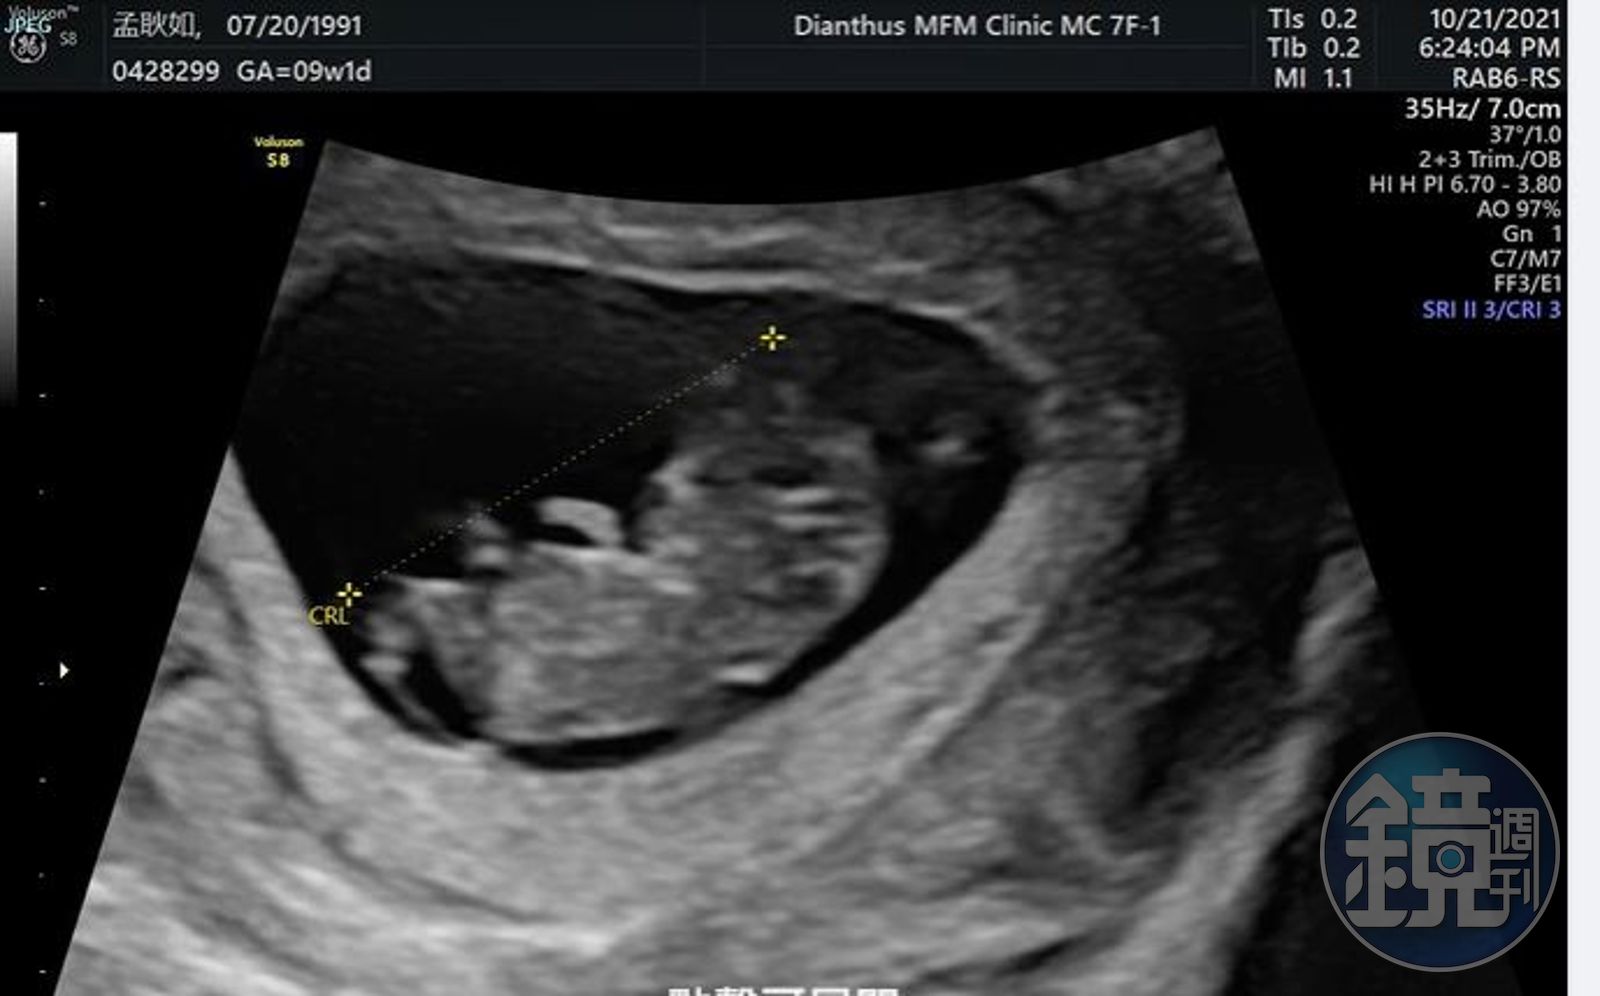

孟耿如在臉書寫道,「終於~~~可以開心的跟大家分享這個消息,目前不知道是小黃瓜還是黃玉米已經在肚子裡三個月了,上面的超音波影片是兩個月的時候他的小手手在跟我們打招呼,覺得肚子裡現在有個六七公分的生命真的很神奇,懷孕到目前一次孕吐都沒有,醫生說我很適合懷孕哈哈哈,但賀爾蒙導致心情沮喪低落是讓我目前覺得最辛苦的地方,不過大家別擔心,老公和朋友都有盡力拉我出門走走,曬曬太陽運動。」